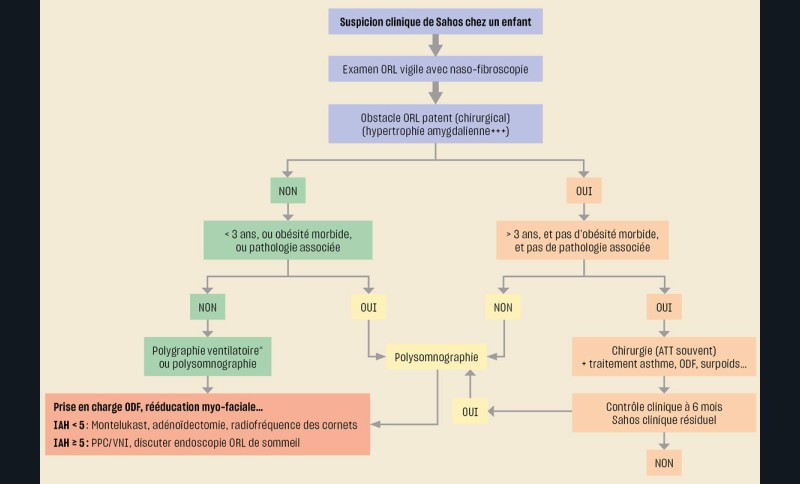

Selon que l’enfant ait ou non un obstacle ORL, soit âgé ou non de plus de 3 ans, et présente des comorbidités ou des pathologies associées, la démarche d’investigation d’un Sahos clinique n’est pas la même (fig. 3). Cependant, dans tous les cas, cette démarche repose sur l’évaluation précise de l’existence ou non d’un obstacle ORL par un médecin familiarisé à l’examen des enfants.

Lorsqu’un enregistrement du sommeil est nécessaire (Sahos clinique sans obstacle ou Sahos clinique avec obstacle ORL chez un enfant à risque), il est réalisé préférentiellement une polysomnographie en milieu hospitalier avec capnographie. En l’absence de facteur de risque, une polysomnographie ambulatoire ou une polygraphie ventilatoire (sans analyse du sommeil) peuvent être proposées si elles sont plus acceptables ou plus accessibles (fig. 4). Tout résultat de polygraphie ventilatoire discordant avec la clinique doit être contrôlé par un enregistrement polysomnographique.

L’existence d’un obstacle ORL pouvant être responsable du Sahos de l’enfant, conduit en général à un geste chirurgical après un avis ORL qui évalue ses indications et contre-indications. Les effets de la chirurgie sont jugés cliniquement après quelques mois et parfois par un enregistrement du sommeil en cas de récidive clinique, surtout si le Sahos préchirurgical était jugé sévère.

En cas de Sahos léger à modéré avec peu ou pas d’obstacle ORL (Sahos résiduel après chirurgie), il peut être testé un traitement médicamenteux par corticoïde topique nasal et/ou un antileucotriène (en France le Montelukast®) [15-17]. La perte de poids chez les enfants obèses a été démontrée comme efficace sur les troubles respiratoires du sommeil de ces enfants et adolescents [18]. Ce n’est qu’en cas d’absence d’indication chirurgicale et d’inefficacité des autres ressources thérapeutiques qu’un support ventilatoire nocturne sera proposé à l’enfant par une équipe expérimentée.